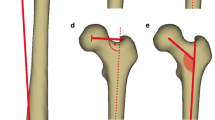

Femoral neck-shaft angle (FNSA)

FNSA (Fig. 6b) angle showed a significant negative correlation with age (r = − 0.526; p < 0.0001) and FHD (r = − 0.596; p < 0.0001). No correlation with gender or side was found. Prompt growth phase was noted at the age of 1 (156.85°–147.4°; 6%) (Table 3).

a Measurement method of femoral neck–shaft angle (FNSA). *Red angle: femoral neck–shaft angle. b Results indicating the development of femoral neck–shaft angle (FNSA) with age. *Reference values: [29] (colour figure online)